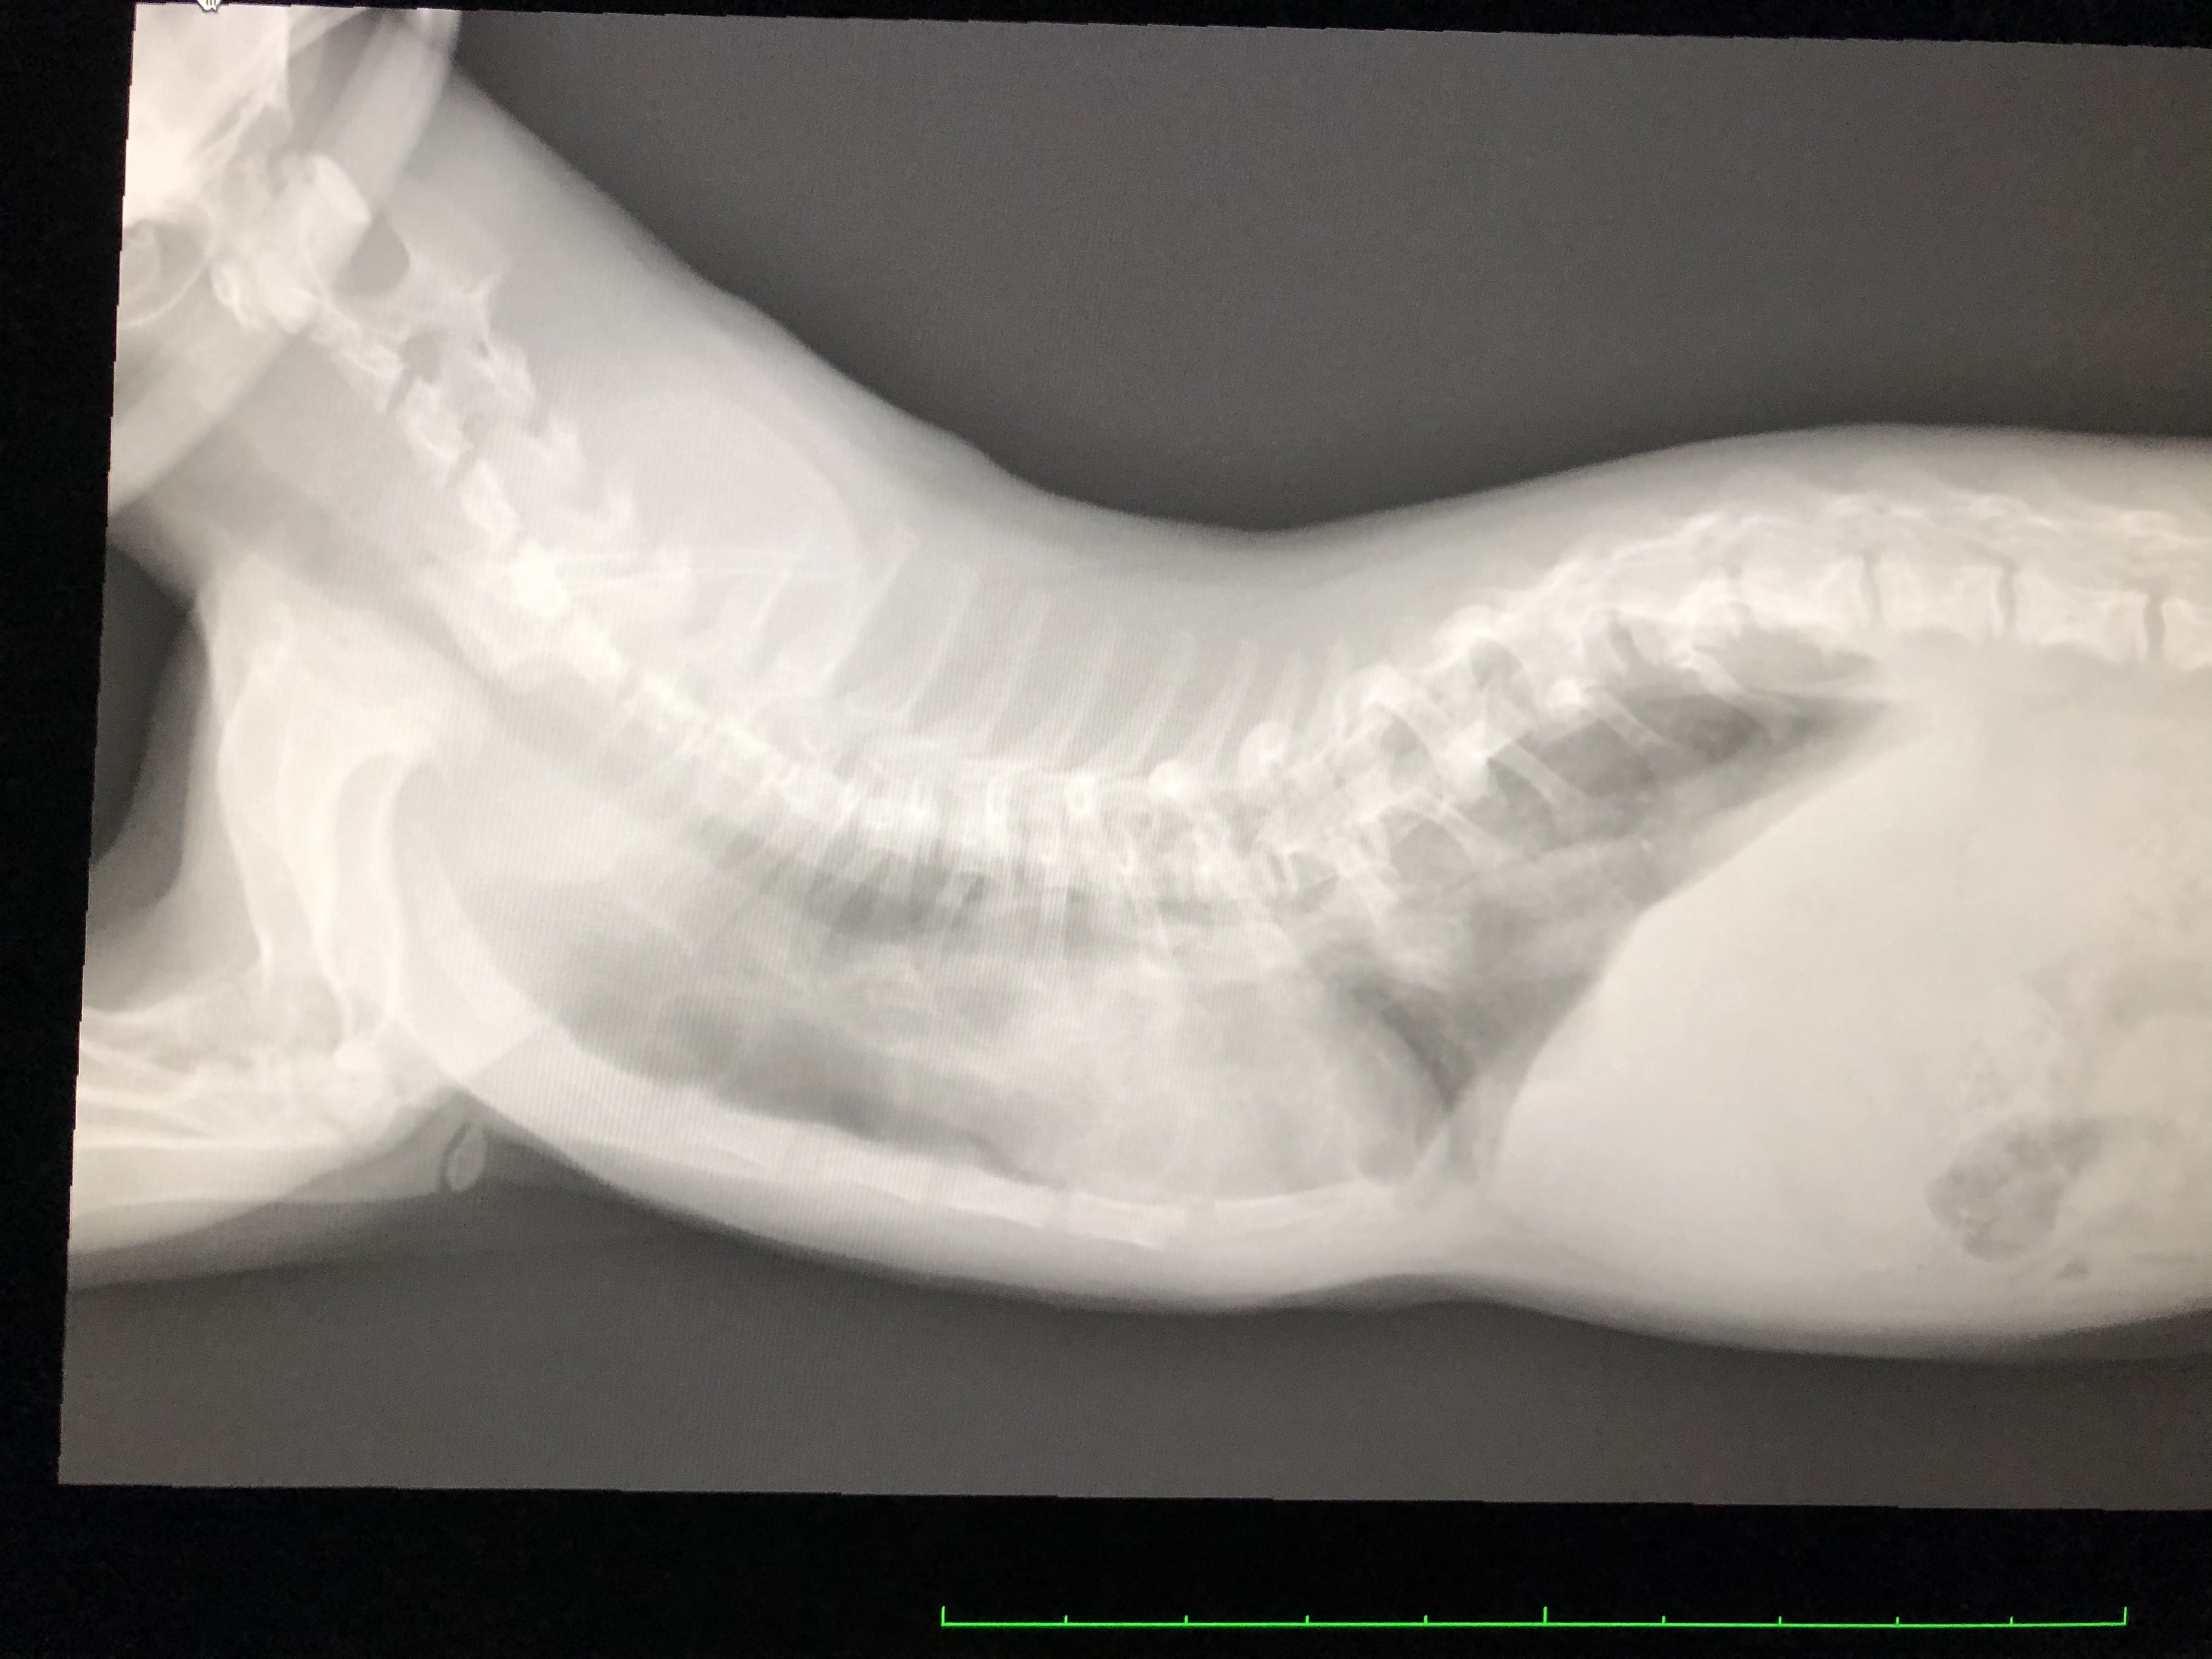

レントゲン、エコー、心電図などなど、いろんな検査をしてもらいました。

春までもたないと言われていた背骨肋骨による胸の空間は愈史郎の成長がゆっくりだったため、悪化していませんでした。

しかし、好転しているわけでもなく、危険は残っていると言われました。

先生の説明では、子猫で体が小さすぎるため、検査結果を見ても、現状ではなんとも言えなく、定期的に検査に行くことになりました。

脊椎の変形が、今後下半身麻痺になるかもしれないと言われました。

(画像は最新の検査時のレントゲンです。)